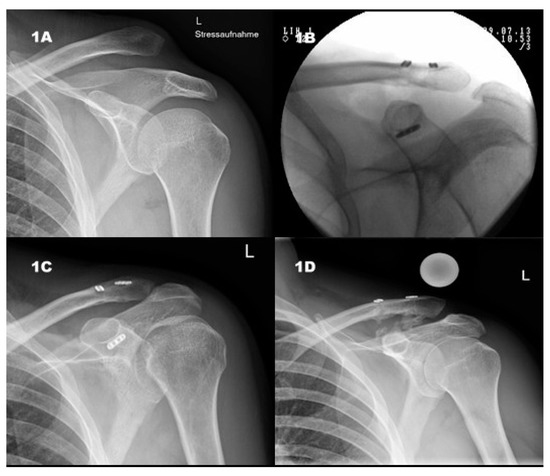

2.2. X-ray

3.3. Radiological Results